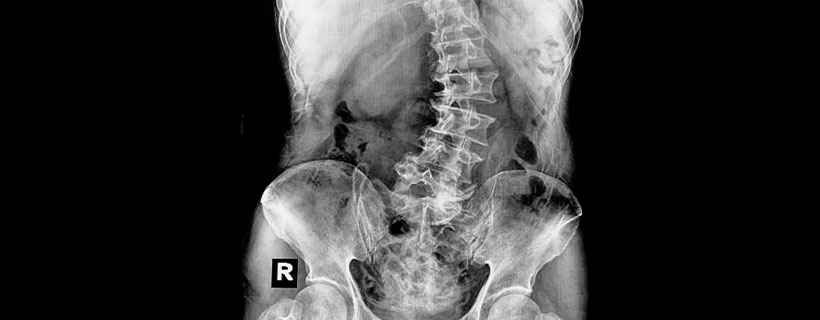

As someone with scoliosis? We understand how much it can interfere with daily tasks such as standing, sitting, walking, or even breathing. Finding relief from scoliosis can be a daunting journey with limited treatment options.

Living with scoliosis can have a tremendous impact on your life, from your emotional state to your ability to perform mundane tasks. Scoliosis is one condition that should be actively managed, or it may worsen if left untreated.